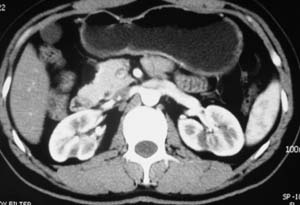

以下是引用子期在2010-3-19 20:47:00的发言:[br]血管畸形的ct增强应该有明显强化,本例并不相符合。本例双肾局部的略低密度影,累及肾盂,局部皮质明显变薄、内陷,增强扫描有轻度的强化,应考虑为炎性病变,患者为年轻男性,累及双肾的感染以结核较常见,可以没有明显的临床症状,尿中有时候也并不能查出什么;肾脓肿常有明显感染中毒症状,本例不符,另外一般的肾盂肾炎或肾小球肾炎通过小便就可确诊,其它还不能排除的是黄色肉芽肿性肾盂肾炎,然而单凭ct一般也很难鉴别。